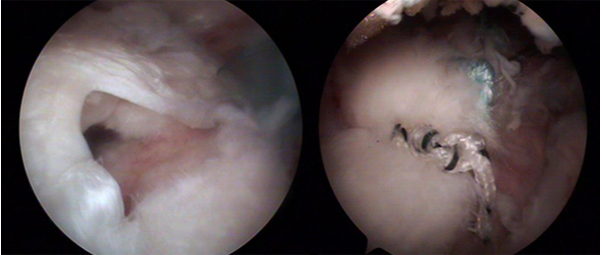

회전근개 파열은 힘줄의 퇴행성 변화, 부상 등으로 어깨를 들고,돌리는 힘줄이 끊어져 통증이 있고 팔을 움직이는 힘이 약해지는 병입니다.

어깨부위에 나타나는 동통이 있으며, 팔을 머리 위로 들 때 심해진다.

손상의 정도에 따라 팔의 근력약화가 유발되며 완전 파열의 경우 팔을 앞으로나 옆으로 들지 못할 수도 있다.